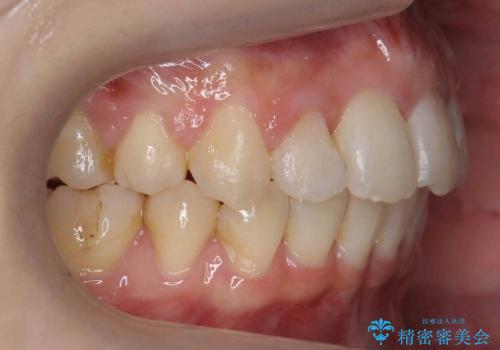

治療の難易度としてはかなり高めでしたが、無事終了することができました。

- 虫歯治療を担当した先生からの紹介。

矯正治療をおすすめし、ちょうど虫歯がひどい歯は抜歯して前歯を下げました。

下顎の大臼歯が前に倒れこんでいたため、矯正用ミニスクリューで後ろに起こしています。